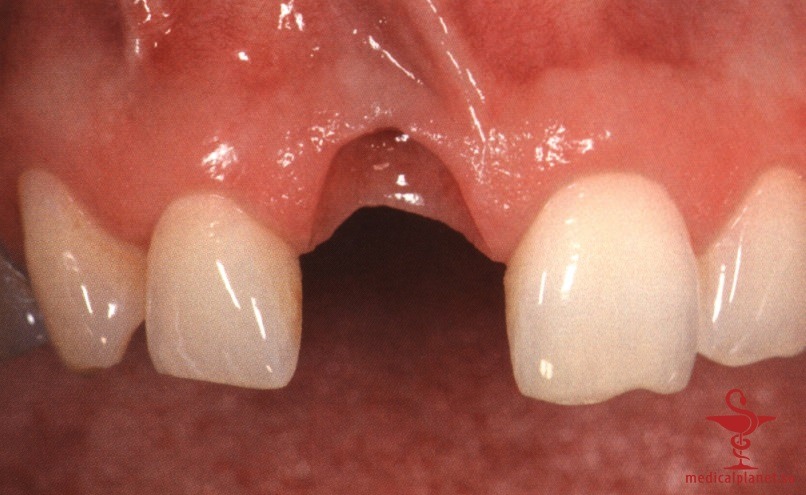

В частности, в эстетически значимой зоне имплантат не следует устанавливать в положении и направлении корня замещаемого зуба, поскольку в большинстве случаев это приведет к слишком вестибулярному положению и избыточному вестибулярному наклону имплантата. Обычно такая ситуация ассоциируется с выраженной рецессией десны, как это описывалось в отдельной статье на сайте (просим Вас пользоваться формой поиска по сайту выше) (рис. 1).

Кроме того, оказалось, что удаление зуба неизбежно сопровождается резорбцией альвеолярной кости, причем в большей степени с вестибулярной, чем с язычной стороны, а немедленная имплантация не позволяет предотвратить этот процесс. В передних отделах челюстей утрата вестибулярной кости часто приводит к неблагоприятному эстетическому результату. Сам факт отслаивания слизисто-надкостничного лоскута также усугубляет резорбцию костной ткани.